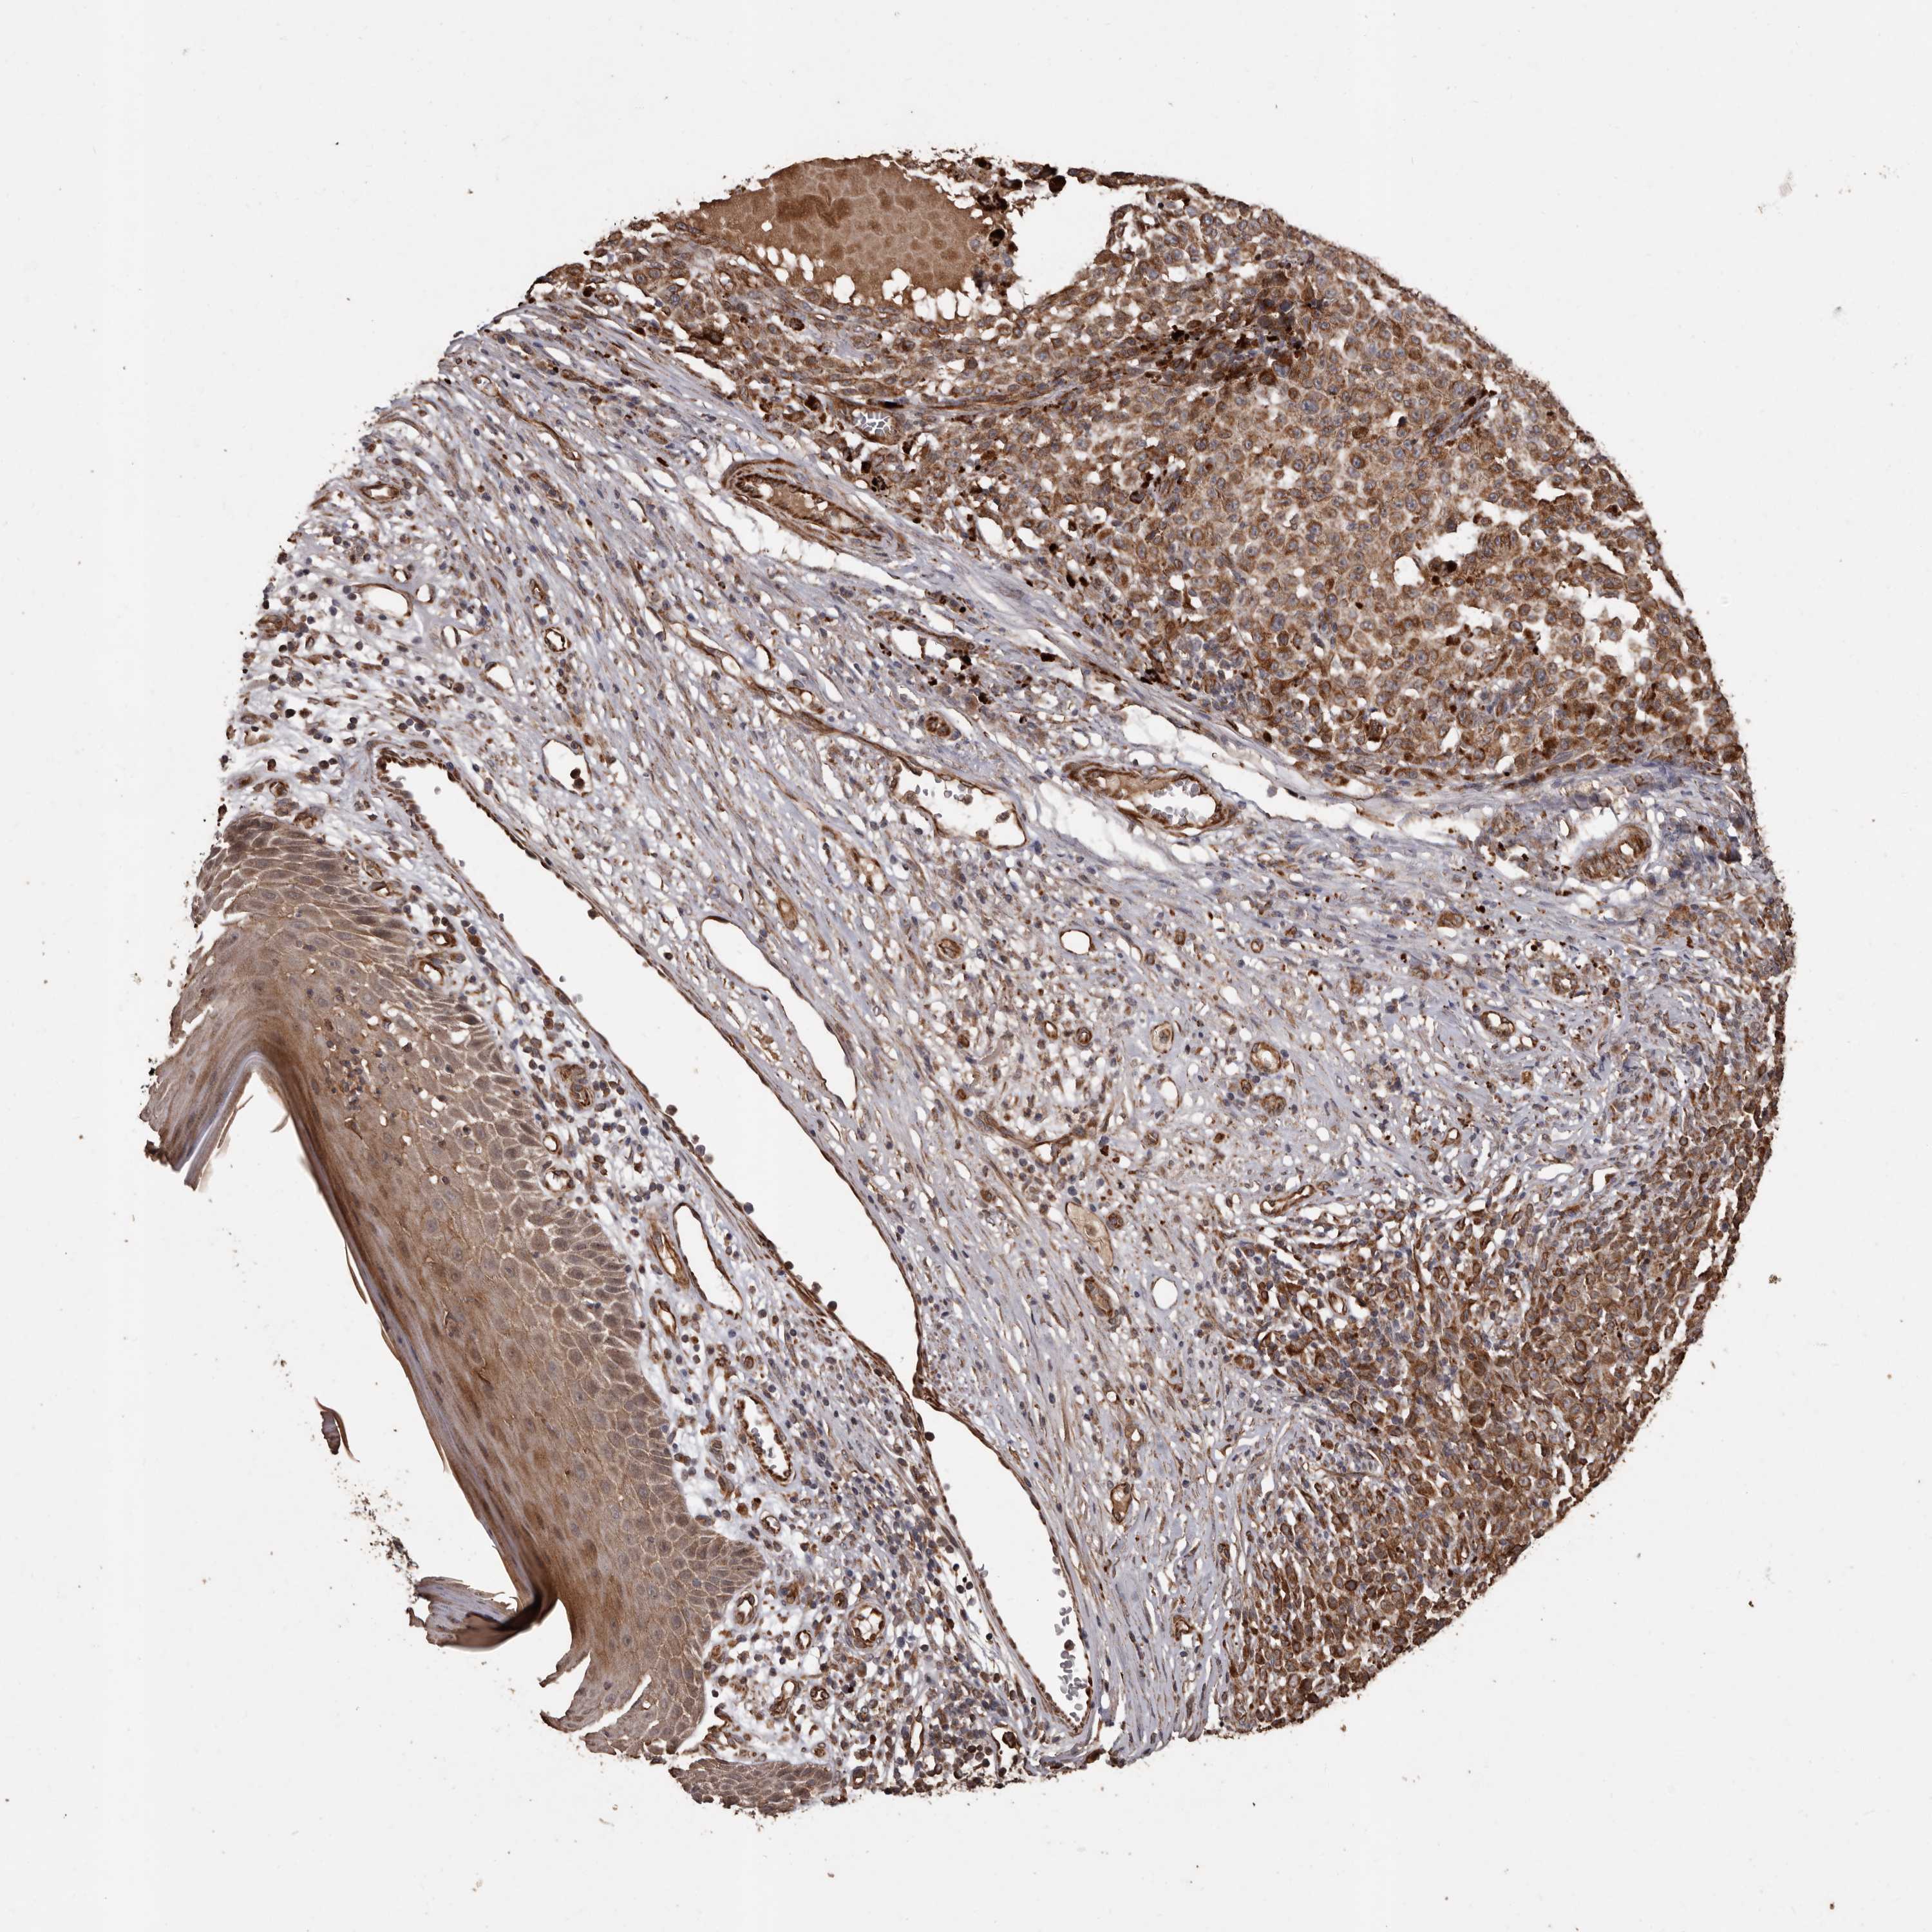

MELANOMA - Protein expressioni

A mouse-over function shows sample information and annotation data. Click on an image to view it in a full screen mode. Samples can be filtered based on level of antibody staining by selecting one or several of the following categories: high, medium, low and not detected. The assay and annotation is described here.

Note that samples used for immunohistochemistry by the Human Protein Atlas do not correspond to samples in the TCGA dataset.

Antibody stainingi

Antibody staining in the annotated cell types in the current human tissue is reported as not detected, low, medium, or high, based on conventional immunohistochemistry profiling in selected tissues. This score is based on the combination of the staining intensity and fraction of stained cells.

Each image is clickable and will lead to virtual microscopy that enables deeper exploration of all samples and also displays staining intensity scores, fraction scores and subcellular localization as well as patient and tissue information for each sample.

Antibody HPA029455

Staining

High

Medium

Low

Not detected

Intensity

Strong

Moderate

Weak

Negative

Quantity

>75%

75%-25%

<25%

None

Location

Nuclear

Cytoplasmic/membranous

Cytoplasmic/membranous,nuclear

Malignant melanoma, NOS

Malignant melanoma, Metastatic site